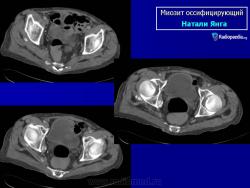

Рентгенологические признаки однотипны для всех форм оссифицирующего миозита; плотный рисунок периферической и менее плотный центральной части повреждения.

При компьютерной томографии визуализируется кальцификация гетеротопической кости, которая продвигается от наружного края образующегося узла в центр.

Рентгенологические признаки однотипны для всех форм оссифицирующего миозита; плотный рисунок периферической и менее плотный центральной части повреждения.